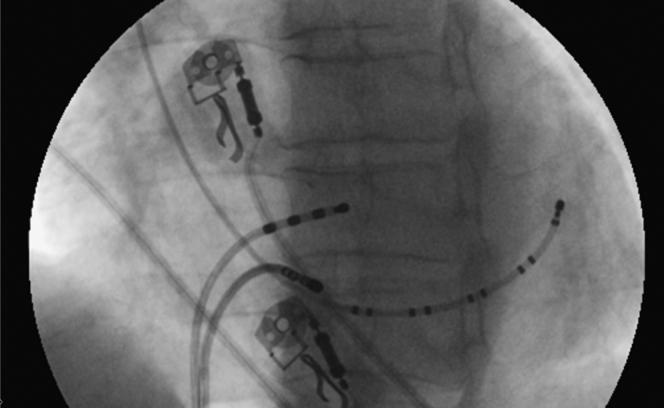

Atrioventricular nodal reentrant tachycardia and the dilemma of reentry circuit components: A proof of concept.

HeartRhythm Case Rep. 2021 Apr 9;7(7):439-441. doi: 10.1016/j.hrcr.2021.03.022. eCollection 2021 Jul.